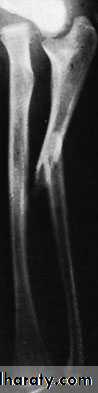

Both bones are broken, either transversely and at the same level or obliquely with the radial fracture usually at a higher level. In children, the fracture is often incomplete (greenstick) and only angulated.X-RAY